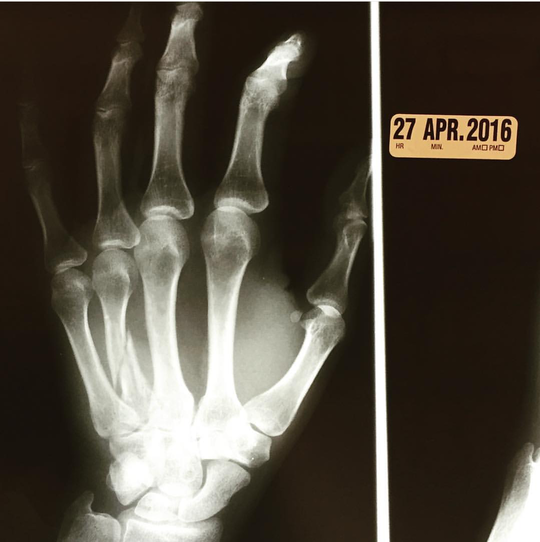

* Maria Kanellis has revealed that she has broken her hand. (Instagram)